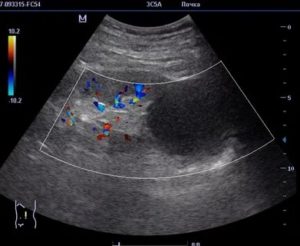

Важно: если проводится доплерография, то при онкологии рисунок сосудов может меняться от полного его отсутствия до чрезмерной васкуляризации при высокой интенсивности цветового сигнала.

3) При ультразвуковом исследовании нашли образование, подозрительное на гипернефрому. Обычно симптомы рака почки и у мужчин, и у женщин хорошо выявляются при УЗИ, особенно при допплерографии.

- при доплерографии в раке выявляется дефект окрашивания, где пропадает нормальная архитектоника почечных сосудов, степень васкуляризации может быть различной – от полного отсутствия изображения сосудов до высокой васкуляризации с множественным усилением цветового сигнала.